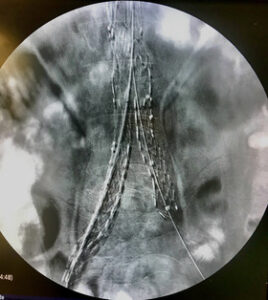

Ανοικτή χειρουργική αποκατάσταση ευμεγέθους συμπτωματικού διανεφρικού ανευρύσματος κοιλιακής αορτής!

Όταν η ενδαγγειακή αποκατάσταση δεν είναι εφικτή , η ανοικτή χειρουργική αποκατάσταση αποτελεί την εναλλακτική θεραπευτική επιλογή.